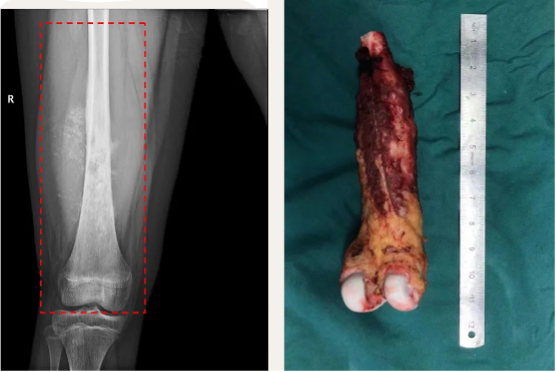

手术包括肿瘤切除和保肢重建两部分。肿瘤切除范围包括股骨瘤段、软组织肿块、以及周围累及的肌肉和软组织,整块切除不能相互分离。在广泛切除边缘切除肿瘤才能达到根治性切除的治疗目标.

整块切除(Enbloc)肿瘤累及的股骨、膝关节近端、软组织肿块和周围肌肉(红色虚线框)。右图为切除后的标本外观照,可见中上段表面深红色部分为与肿瘤相邻的肌肉组织